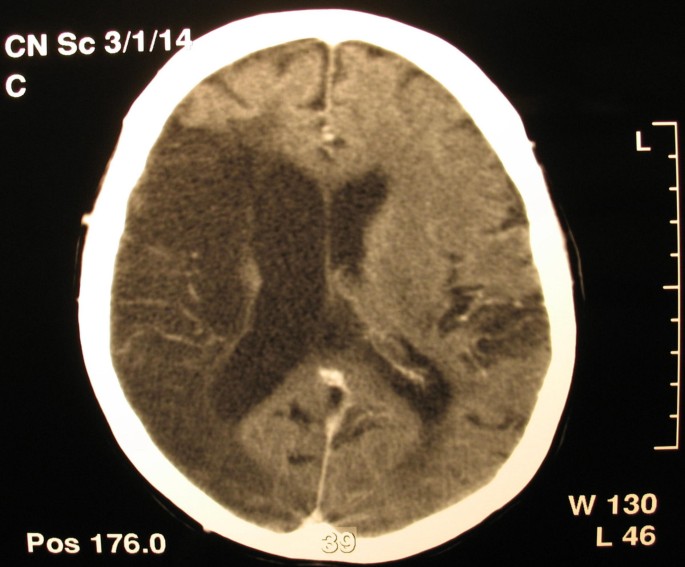

A 65 year old woman was admitted to our hospital with disturbances of consciousness ensued during the last two days. She had been suffering from mitral stenosis for 15 years and was under medical supervision, receiving digoxin, furosemide and warfarin. She had suffered three embolic strokes over the last 5 years. At present the first clinical examination revealed Glasgow Coma Scale (GCS) of 6, left hemiplegia, atrial fibrillation, low blood pressure of 70/40 mmHg and temperature of 38.5°C. With the diagnosis of an imminent stroke the patient underwent emergency CT scan of the brain and thorax. Brain scan disclosed extensive ischemic damage to the right brain hemisphere (Figure 1), compatible with preexisting lesions. The CT of the thorax revealed an enlarged left atrium and the existence of a distinctly outlined mass of 10.3 cm × 6.3 cm × 6.5 cm in the left atrium (Figure 2) Echocardiography confirmed the presence of the mass and severe mitral valve stenosis with valve opening of <1 cm2 (Figure 3)